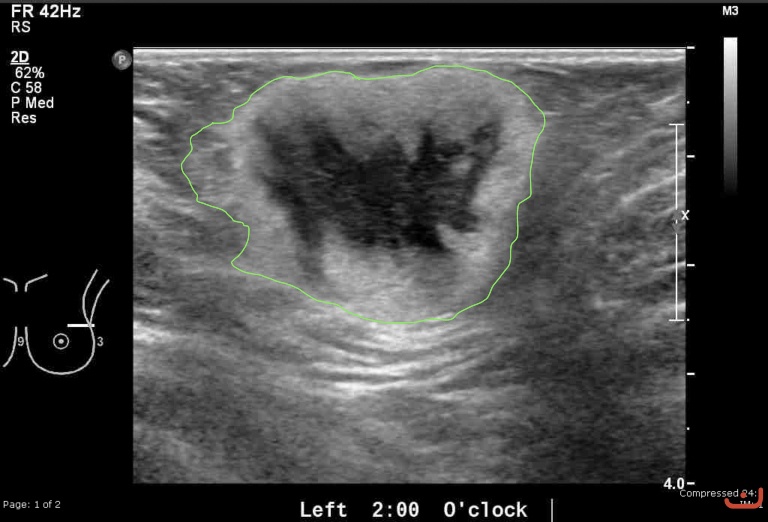

Case 41-G1

Malignant solid mass

Friday, 22 May 2015

186.67 KB (768 x 522 px)